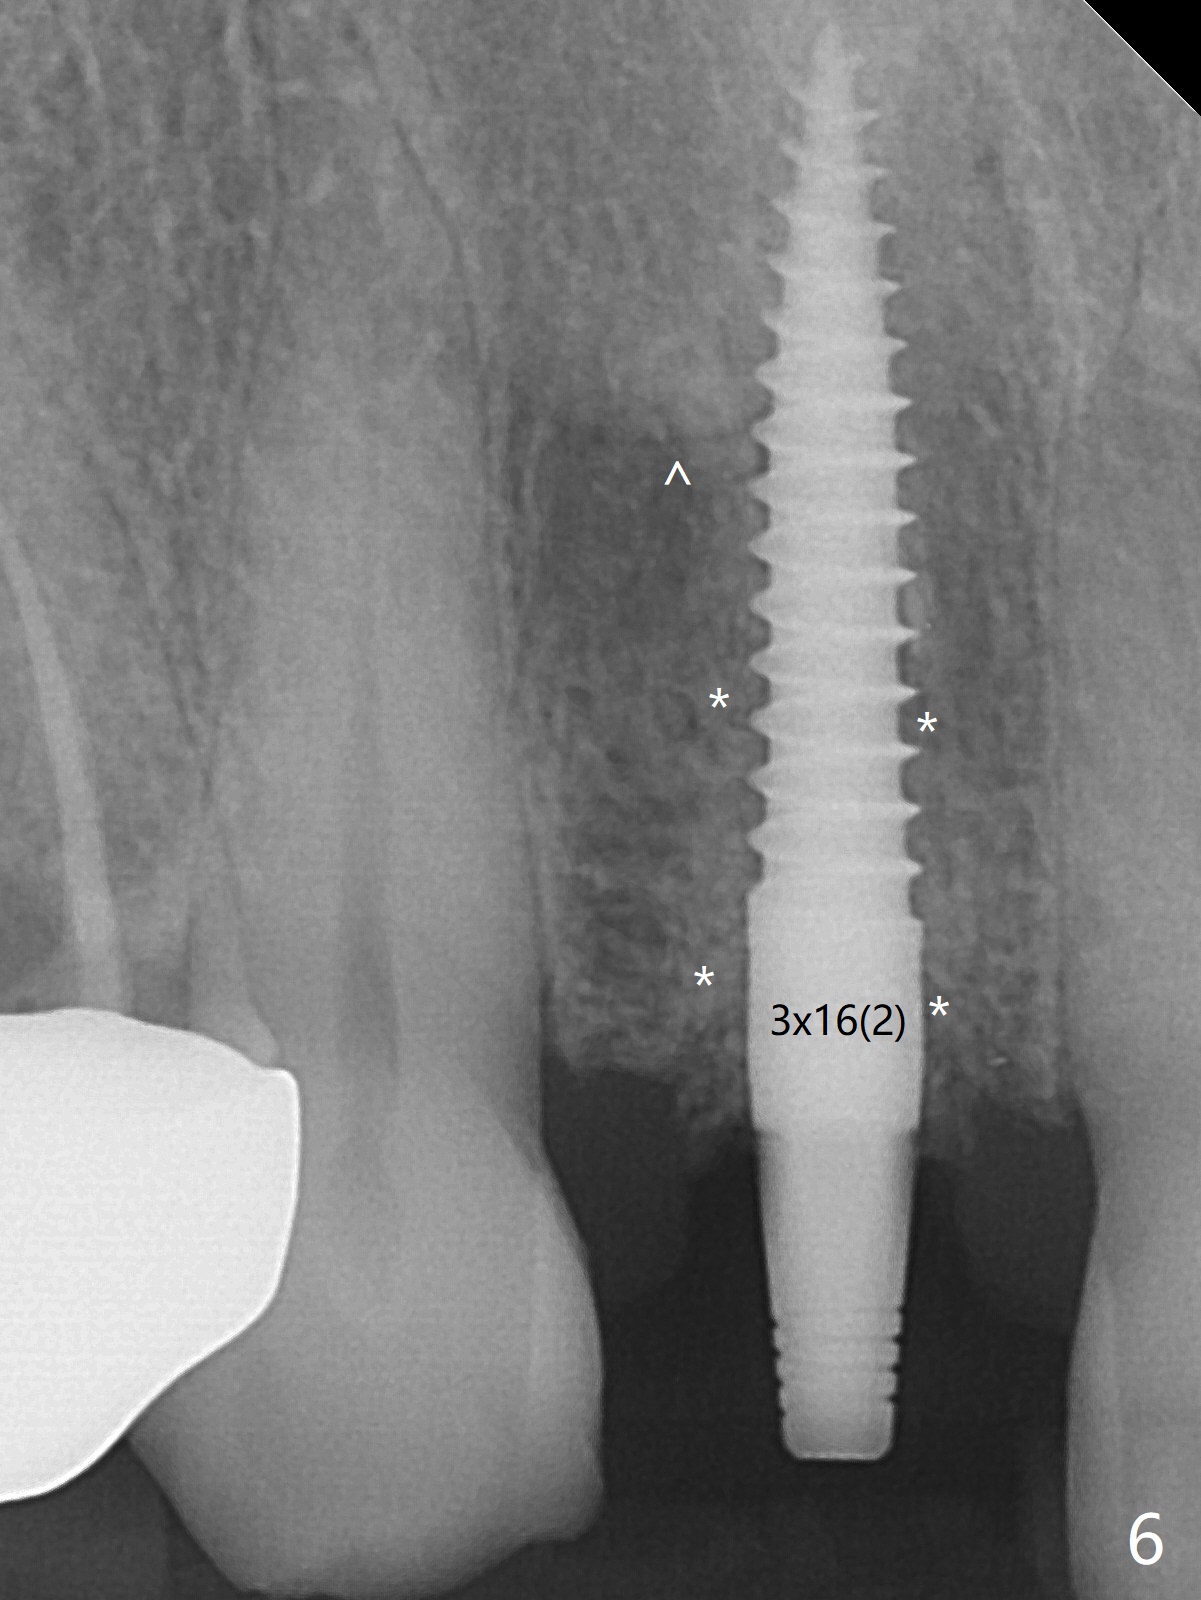

The rebonded crown at #7 debonds in a few days. There is deep anterior overbite and buccal concavity (Fig.1 *). The equigingival fracture (Fig.1,2) seems difficult to restore considering lack of posterior support (lower RPD in Fig.1). Buccal shield is tried in spite of the long root. It is not easy to tell whether the infected apex is removed due to the deep socket. In fact the apical buccal plate perforates because of use of surgical handpiece. Finally the buccal shied is removed. PA confirms the retained apex (Fig.3 *). The initial osteotomy with 1.5 mm drill in place is off trajectory (Fig.4). After adjustment of the trajectory of osteotomy (Fig.5), a 3x16(2) mm 1-piece implant is placed within normal limit (10-15 Ncm, Fig.6)). In fact bone graft is placed before (Fig.6,7 arrowhead; to repair apical buccal plate perforation) and after (Fig.6 *) implantation. The gingiva (including papillae) remains normal around the provisional 3 months postop (Fig.8). The bone graft becomes more organized 3 months postop (Fig.9), continues to do so 4.5 months postop (Fig.10) and becomes dense coronally 9 months post cementation (Fig.11: *).